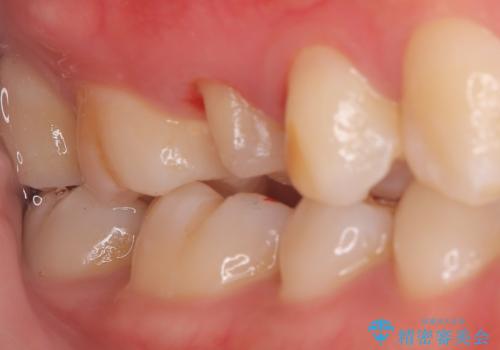

- 主訴:他院で根っこの治療を行っていたところ、根が細く治療が難しいと言われてしまった

右上5番目の歯が根管治療途中となっており、前医院にて根管が狭く治療が難しいと言われてしまいセカンドオピニオンで当院にいらっしゃいました。

右上5番レントゲン写真上では根管が確認しずらく、根管の狭窄が予想されました。マイクロスコープを使用し、根尖部まで器具を到達させ十分根管洗浄を行うことができました。